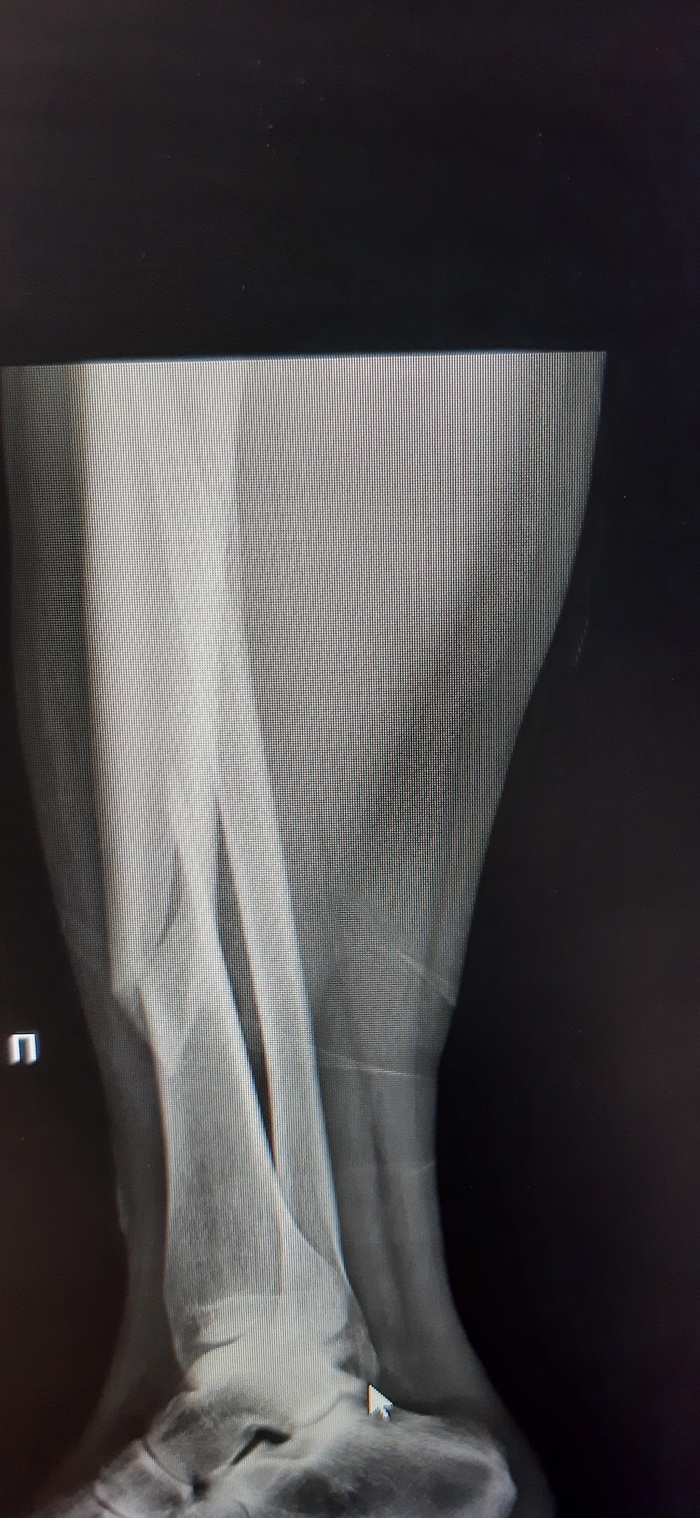

Ну и очень много рентгеновских снимков